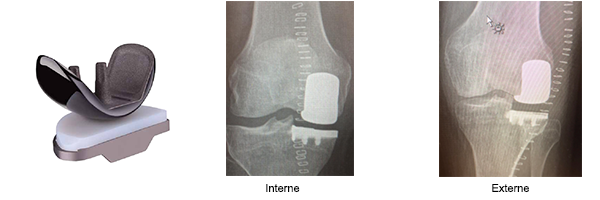

Le bilan comprend des radiographies standards en charge, une goniométrie pour mesurer l’axe mécanique.

Eventuellement un arthroscanner ou IRM afin de cartographier votre arthrose.

Avec ces examens, on peut ainsi prévoir un traitement sur mesure de l’arthrose.